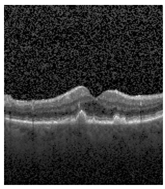

The publicly accessible dataset [27] encompasses detailed cross-sectional images of living patients’ retinas, which have been classified into four distinct categories: Normal, CNV, Drusen, and DME. These categories are visually represented in Figure 3. The dataset comprises a grand total of 84,492 images, distributed as follows: CNV contains 37,457 images, Normal contains 26,567 images, DME includes 11,600 images, and Drusen encompasses 8868 images.

Figure 3. Illustrative examples from the retinal image dataset are presented. Figure (a) showcasing Choroidal NeoVascularization, characterized by the presence of neovascular membranes (indicated by white arrowheads) along with associated sub-retinal fluid (marked by arrows). Figure (b) illustrates Diabetic Macular Edema, which manifests as intra-retinal fluid associated with retinal thickening (denoted by arrows). Figure (c) displays multiple instances of drusen (highlighted by arrowheads), while Figure (d) illustrates a normal, pristine retina with an undisturbed foveal structure and no signs of retinal fluid or edema.